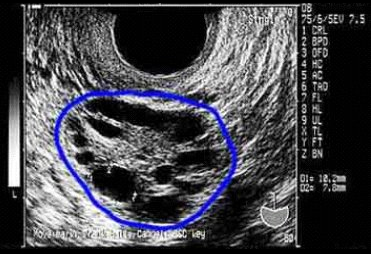

- Ovario poliquístico: en una ecografía se observa la presencia de 12 o más folículos, de diámetro entre los 2-9 mm y/o volumen ovárico mayor de 10 mm.

Ecografía ovárica

Hasta un 80% de los casos se observa un crecimiento bilateral de los ovarios (> 10 ml de aumento de volumen), con presencia de más de 12 folículos de un diámetro entre 2-9 mm subcorticales rodeados de un estroma denso.

La presencia de ovarios poliquísticos es uno de los criterios diagnósticos, pero su presencia no es indispensable para el diagnostico del SOP.